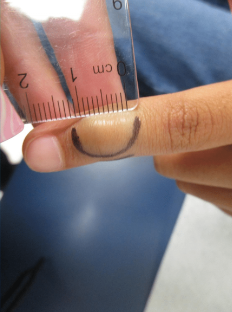

CHIEF COMPLAINT: Two Brown Spots on the Left Hand

CLINICAL HISTORY: The patient reported a 5-year history of two brown spots on the left hand. Initially, the lesions were blue and attributed to ink stains although the patient denied contact with any staining chemicals or dyes. The “spots” increased in size over a two-year period and changed from blue to brown in color. She denied recent travel and had no history of skin cancer or atypical nevi. Family history revealed a brother with a history of melanoma. Her medications included premarin and glucosamine and she denied any allergies.

Two brown velvety irregularly pigmented patches on the palm of the left hand.